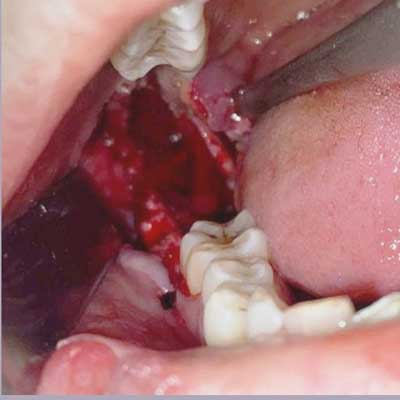

This is a representative case of an Odontogenic Keratocyst which was thankfully, caught early, during a routine dental xray (which is often the case)

The entire cyst was removed in-toto using an intra-oral approachalong with the offending tooth. There was no external skin incision and the healing was uneventful.